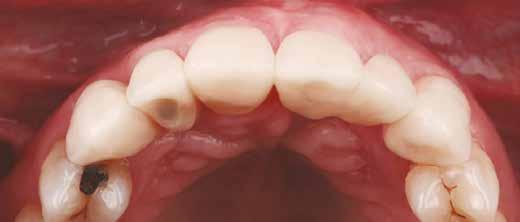

heléssel vagy anélkül). Az első páciensnél gyökérreszorpció miatt szükségessé vált a jobb felső premolárisok és az első moláris eltávolítása (1. a–b ábrák). A második páciensnél a bal felső második premoláris frakturát szenvedett (1. c–d ábrák) Az átfogó tervezést és diagnosztikát CBCT-felvétel segítségével végeztük (2. a–c ábrák), a posztoperatív kontroll és az utánkövetés időszakában pedig periapikális röntgenfelvételeket készítettünk. A jelen tanulmányban résztvevő valamennyi páciens nemdohányzó volt, jó, vagy gyógyszeresen jól karbantartott általános egészségi állapotnak örvendett. A hatékony plakk-kontroll ellenére műtét előtt mindkét páciensnél végeztünk supragingivális depurálást és gyökérsimítást.

A fogak eltávolítása minimálinvazív módon történt, amelynek során a parodontális rostokat egy periotom segítségével átvágtuk, így lebenyes feltárásra nem volt szükség (3. a–b ábrák) . Az implantátumokat a frissen eltávolított fogak alveolusaiba ültettük be. A foghúzást követően minden alveolust alaposan ellenőriztünk az endodontiai, vagy parodontális eredetű gyulladásos szövetmaradványok eltávolítása érdekében, majd fiziológiás sóoldattal bőségesen átöblítettük. Megfelelő előfúrást követően a kerámiaimplantátumokat 30 fordulat/perc sebességgel és 35 Ncm behajtási nyomatékkal helyeztük be (4. a–b ábrák) . A réseket csontpótlóval töltöttük ki (Maxresorb ® 0,5–1,0 mm szemcseméret, 0,5 cm 3 térfogat, Straumann ®; 6. ábra ).

Azonnali ideiglenes fogpótlás

A műtétet követően önkötő akrilátból ideiglenes koronákat készítettünk, amelyeket cementtel rögzítettünk a cirkónium-dioxid ideiglenes fejeken (CR Zi Pillar®, 7. a–c ábrák ).